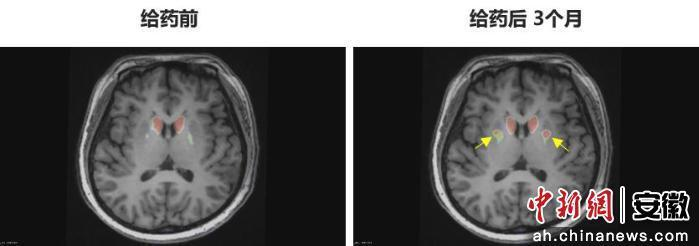

术后一个月,变化悄然发生:长期的“连续剧式梦”消失,睡眠质量显著提升,抑郁情绪也逐渐消散。最让她震撼的是术后脑部影像——医生指出的“新生亮点”,是成功移植的多巴胺能神经细胞,“像小火苗,点亮了我心里熄灭多年的地方”。

图为李女士 PET-DAT/MRI融合图像术前与术后三个月对比。